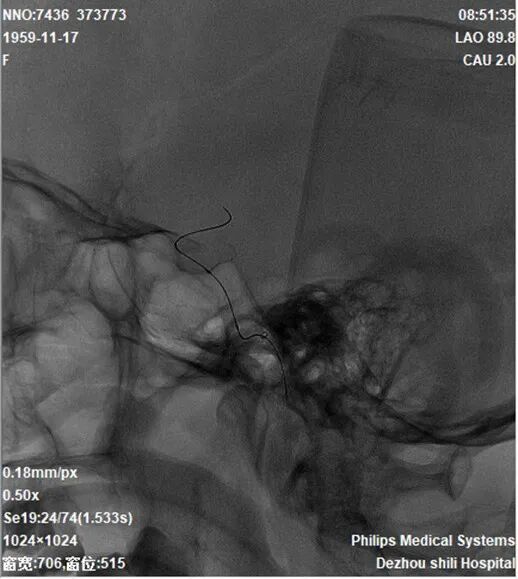

导引导管到位,导丝通过病变,球囊通过病变。

导丝怎么扩【载药时代 球扩天下】NOVA DES®颅内药物洗脱支架在颈内动脉颅内段重度狭窄的应用二例!_https://www.jmylbn.com_新闻资讯_第28张

球囊扩张过程。

导丝怎么扩【载药时代 球扩天下】NOVA DES®颅内药物洗脱支架在颈内动脉颅内段重度狭窄的应用二例!_https://www.jmylbn.com_新闻资讯_第29张